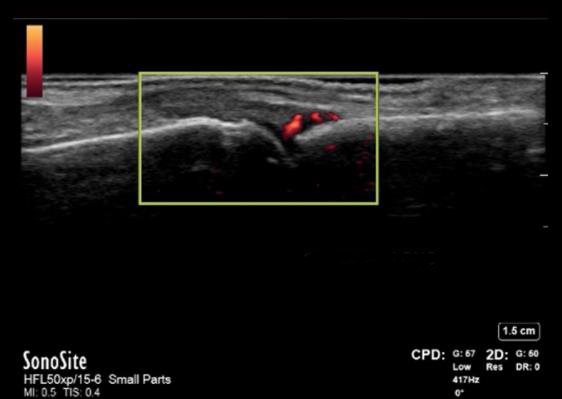

手部 MCP 关节滑膜炎早期 RA(血清阴性)图像

2 MCP 长